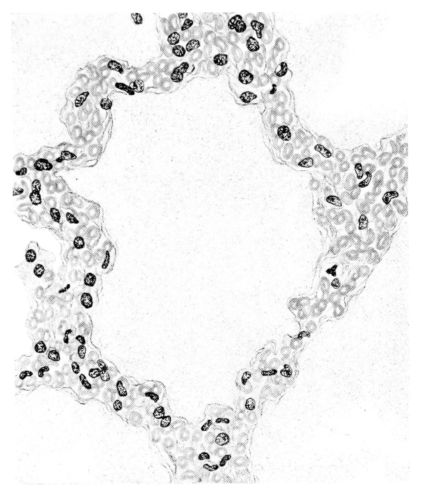

FIG. I. AUTOPSY NO. 99. ACUTE HEMORRHAGIC AND ULCERATIVE LARYNGOTRACHEITIS.

FIG. II. AUTOPSY NO. 98. DRAWING OF A SECTION THROUGH A TRACHEA SHOWING NECROTIZING HEMORRHAGIC INFLAMMATORY PROCESS OF THE MUCOSA.

FIG. III. AUTOPSY NO. 90. DRAWING FROM A LESION OF THE TRACHEA (SOMEWHAT OLDER THAN THAT ILLUSTRATED IN FIGURE II). THE MUCOSA IS ENTIRELY LACKING. CONGESTION AND EDEMA ARE THE STRIKING FEATURES IN THE SUBMUCOSA. THE NECROTIZING PROCESS HAS EXTENDED INTO THE MUCUS GLANDS. THIS IS SHOWN IN THE LOWER PICTURE.